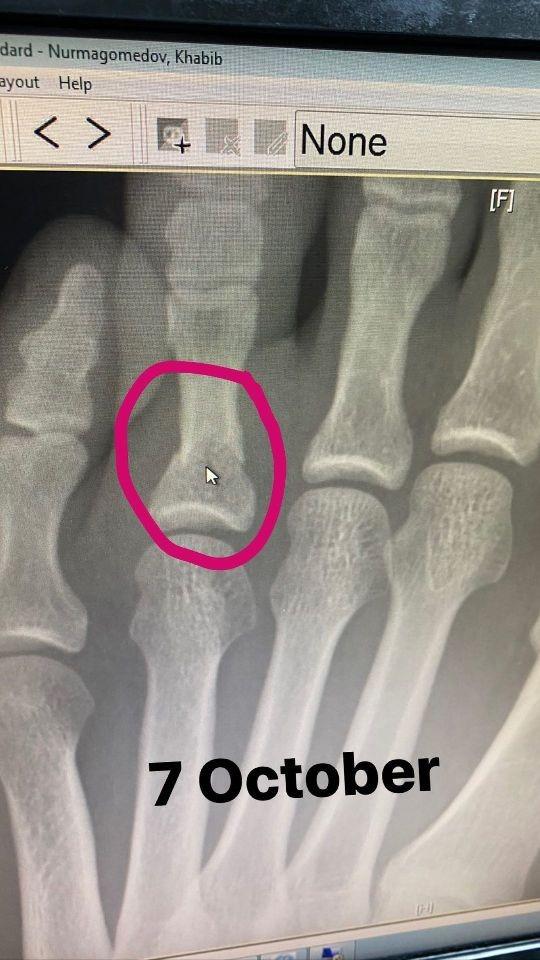

Маалыматка ылайык, биринчи сүрөт 7-октябрда тартылган рентген сүрөт болсо, экинчи сүрөт 8-октябрда ошол эле жаракат алган буту сыртынан тартылган.

Буга чейин UFC уюмунун президенти Дана Уайт Хабиб Нурмагомедов Жастин Гэйтжи менен боло турган беттешке үч жума калганда бутун сындырып алып, эч кимге айтпай дарыланып чыккандыгын айтып таң калган.